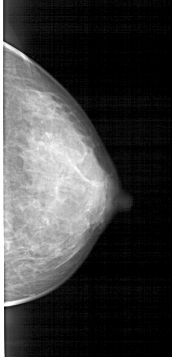

A_1446_1.LEFT_MLO

LEFT_MLO LINES 5341 PIXELS_PER_LINE 2461 BITS_PER_PIXEL 12 RESOLUTION 43.5 OVERLAY